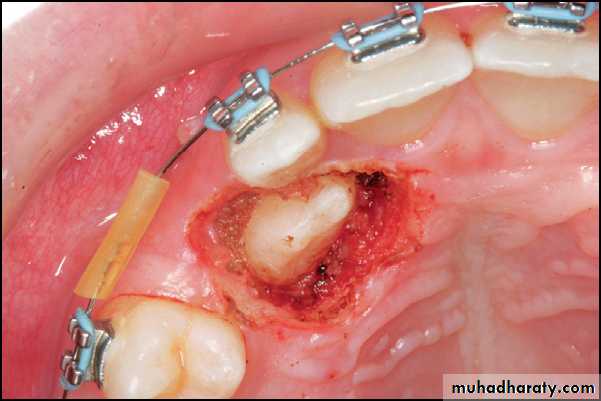

Two basic approaches, either a “closed” or “open” technique, are used to provide access to the impacted canine.1)) In the “closed eruption” technique, the crown of the canine is exposed, the orthodontic eruption device is attached to the crown, and the flap is sutured back over the tooth, leaving only the eruption chain exposed for orthodontic manipulation. The eruption chain is usually exited through either the crestal incision or the extraction site of the primary canine and ligated to the archwire or brackets on the adjacent teeth.

Flap, closed eruption procedure for exposure (A), and bonding (B) of palatally impacted canine. C, Flap sutured back over the tooth, leaving only the eruption chain exposed.

2)) In the “open eruption” technique, the crown of the impacted tooth is exposed with either an opening cut into the overlying tissue without flap reflection, or a flap is reflected, a window cut in it, and then the flap is repositioned.

Flapless open procedure (A), with periodontal dressing applied (B) for palatally impacted canine